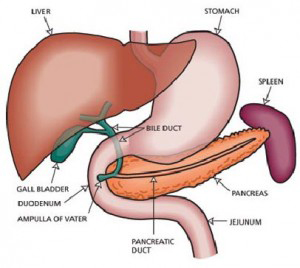

Δυστυχώς η πλειοψηφία των ασθενών με καρκίνο του παγκρέατος δεν μπορούν να υποβληθούν σε χειρουργική θεραπεία, λόγω της τοπικής προσβολής παρακείμενων ζωτικής σημασίας δομών όπως η άνω μεσεντέρια αρτηρία, ή λόγω ύπαρξης μεταστατικής εντόπισης.

Δυστυχώς η πλειοψηφία των ασθενών με καρκίνο του παγκρέατος δεν μπορούν να υποβληθούν σε χειρουργική θεραπεία, λόγω της τοπικής προσβολής παρακείμενων ζωτικής σημασίας δομών όπως η άνω μεσεντέρια αρτηρία, ή λόγω ύπαρξης μεταστατικής εντόπισης.

Στα ανεγχείρητα νεοπλάσματα του παγκρέατος έχουν χρησιμοποιηθεί θεραπευτικές προσεγγίσεις συμπεριλαμβανομένης της ακτινοθεραπείας, της χημειοθεραπείας και της συνδυασμένης ακτινοθεραπεία-χημειοθεραπείας (9 ..10 ..11 ..12 ..13, 14). Ενώ η παρηγορητική θεραπεία και η παράταση προσδόκιμου επιβίωσης μπορούν να επιτευχθούν με αυτές τις προσεγγίσεις, δεν υπάρχει ουσιαστικά καμιά θεραπευτική δυνατότητα.